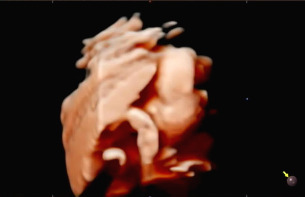

다른 부분을 확인하고 태아의 얼굴을 보기 위해 초음파를 시작하는데 아기가 자궁벽을 향해 얼굴을 붙이고 있어서 초음파에서 얼굴을 보기 힘들었다. 입체 초음파로 생김새를 정확히 보기 위해서는 태아가 양수가 많이 있는 방향으로 얼굴을 가리지 않아야 한다. 햇님이는 벽에 얼굴을 붙인 것뿐 아니라 손으로 얼굴을 가려서 더욱 보기가 힘들었다. 사실 입체 초음파를 보기 전 일반 초음파를 확인할 때 얼굴을 보기 힘들었어서 이번에도 어려울 거라고 예상은 했었다. 그래서 초음파를 확인하는 선생님이 나의 배를 열심히 흔들었다. 태아가 양수의 흔들림에 자세를 바꾸기를 바라며 나의 배를 흔들고 눌렀는데 초음파에서 얼굴 정면을 볼 수 없었다.

복부를 흔들고 누른다고 엄마인 나까지 배가 아팠는데 괜히 얼굴 한번 보겠다고 태아에게까지 스트레스를 준 것은 아닌가 걱정했다. 평소 태동이 격렬했던 햇님이가 걱정되는 마음 탓에 태동이 줄어든 것 같아 초음파를 시행한 당일에 열심히 태담을 했다. 만약 내가 또 임신을 하게 된다면 입체 초음파를 시행하지 말아야겠다고 생각했다.